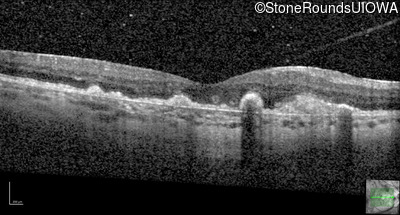

Malattia Leventinese (IIJ)

Malattia Leventinese (IIJ)

This 43 year old woman has experienced a gradual reduction in her central vision for the past 3 years.

| Malattia Leventinese | EFEMP1 | Arg345Trp CGG>TGG | AD |